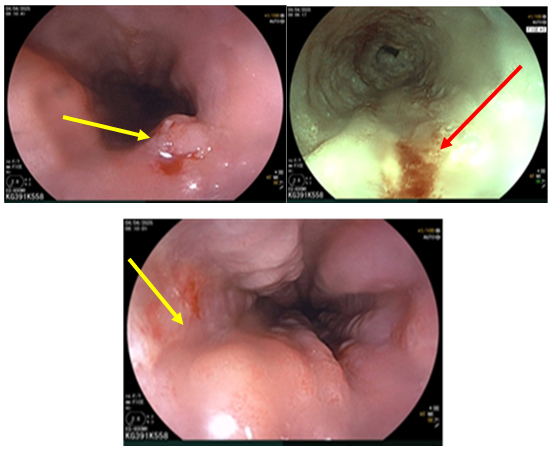

– Nội soi thực quản (Tháng 03/2025): Cách cung răng trên 40cm có đám niêm mạc khác màu kích thước ~ 3cm (sinh thiết ống 1). Cách CRT 38cm có đám thứ 2 kích thước ~ 2cm (sinh thiết ống 2). Cách cung răng trên 25 – 30cm có đám niêm mạc gồ ghề, khác màu chạy vòng gần hết chu vi (sinh thiết ống 3). Hạ hầu có sẹo và nhiều đám loạn sản mạch (sau xạ trị). Dạ dày: viêm dạ dày. Kết luận: Tổn thương loạn sản thực quản (3 vị trí) – viêm dạ dày – tổn thương hạ hầu sau xạ trị.

Hình 4: Nội soi thực quản hình ảnh tổn thương nhiều vị trí (mũi tên vàng và đỏ)